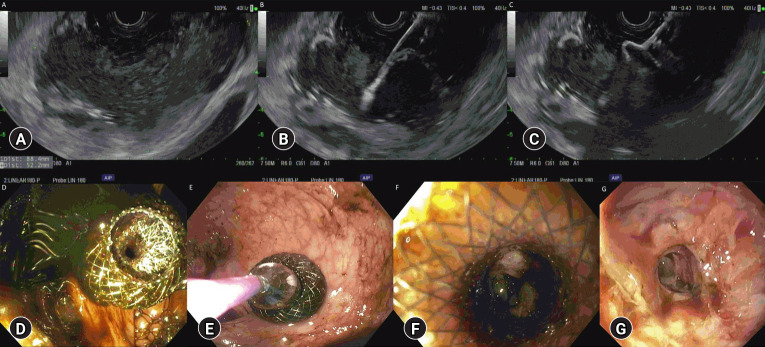

超声内镜引导下经直肠引流治疗儿童盆腔深脓肿安全有效。

Endoscopic ultrasound-guided transrectal drainage of deep pelvic abscesses is safe and effective in children.